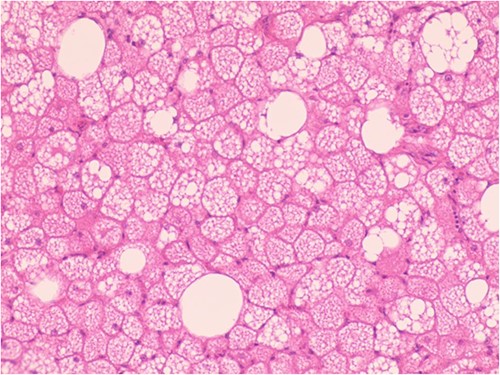

The patient was admitted to the hospital due to the discovery of an inguinal mass that had been present for 1 year. The patient initially noticed swelling in the groin area a year ago. Over time, it gradually increased in size and caused localized discomfort. During the examination, a mass the size of a hen’s egg was felt in the right inguinal region. It had limited mobility and was not tender. No significant abnormalities were found in the motion or sensation of the right lower limb. Ultrasonography showed an isoechoic mass within the muscle tissue of the left inguinal region. Unenhanced and enhanced magnetic resonance imaging (MRI) scans suggested a well-defined intermuscular mass at the root of the right thigh. The mass showed low signal intensity on diffusion-weighted imaging and isointense-to-slightly hyperintense signal post-enhancement (Fig. 1). The patient then underwent excisional biopsy. The excised tissue showed a capsulated, lobulated, soft and greasy mass with a brownish-yellow cut surface. Ultrastructural examination revealed large multivacuolated adipocytes with eccentric nuclei, cytoplasmic acidophilic granules and small lipid droplets. Additionally, abundant blood vessels were present within the stroma. Immunohistochemistry results showed positive staining for S100 protein and negative staining for CD34 (Fig. 2).

Hypertrophic adipoid cells with abundant interstitial vessels (HE*400).